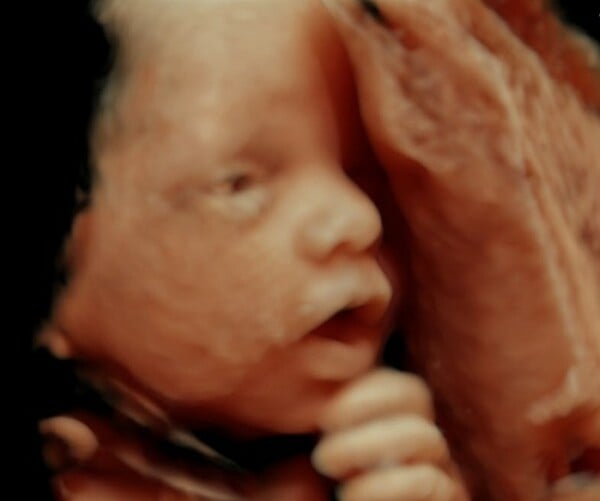

Οι 3D υπέρηχοι δεν είναι κάτι καινούργιο. Αυτό που είναι όμως καινοτόμο στην τεχνολογία που η GE Healthcare εφαρμόζει, είναι κάτι που που φέρνει στην επιφάνεια μια τελείως διαφορετική οπτική. Πέραν της 3D και 4D απεικόνισης, το φως που διαχέεται ελεγχόμενα επιτρέπει στους γονείς να δουν με εκπληκτική λεπτομέρεια χαρακτηριστικά του παιδιού τους, εκφράσεις, κινήσεις, ακόμη και αντιδράσεις που μέχρι πρότινος ήταν αδύνατο να αποτυπωθούν.

Αυτό που όλοι γνωρίζαμε και είχαμε συνδυάσει σαν υπέρηχο ήταν μια απεικόνιση στην οποία οι περισσότεροι χωρίς τις κατάλληλες εξηγήσεις και την ιατρική καθοδήγηση, δεν μπορούσαν στην πραγματικότητα να διακρίνουν κάτι. Η νεαρή μητέρα μπορούσε τώρα να δει τον γιο της να κινείται σαν άνθρωπος, να διακρίνει το πρόσωπό του, τη μύτη του, τα χέρια του, με λεπτομέρεια που συναρπάζει.

Μέχρι πρόσφατα η τεχνολογία δεν ήταν ευρέως διαθέσιμη παρά μόνο σε μεγάλες μαιευτικές κλινικές. Φέτος, ακόμη και οι μικρότερες, αρχίζουν να τη λειτουργούν και οι γονείς την υποδέχονται με ενθουσιασμό και ανακούφιση. Αφενός αποτελεί ένα σπουδαίο εργαλείο ιατρικής παρακολούθησης της κύησης και της ανάπτυξης ενός εμβρύου από τον τρίτο κιόλας μήνα και αφετέρου είναι ένας ακόμη συνδετικός κρίκος των γονιών με το παιδί τους. Οι δεσμοί με το "άγνωστο" μωρό στην κοιλιά μιας μητέρας γίνονται ακόμη πιο ισχυροί, οι όποιες αμφιβολίες και αγωνίες μειώνονται στο ελάχιστο και τα συναισθήματα διογκώνονται.

Η γιατρός που χειρίζεται το μηχάνημα υπέρηχων περιγράφει την πρώτη φορά που οι γονείς έρχονται σε τόσο στενή επαφή με το μωρό τους: "Στην αρχή θα ακούσουν την καρδιά και θα επικρατήσει μια σιγουριά πως το μωρό είναι υγιές και ζωντανό. Μόλις όλα είναι κατάλληλα, αναλαμβάνει η τεχνολογία HDlive και τότε βλέπεις την ανάσα τους να κόβεται. Είναι δυνατές στιγμές που μοιραζόμαστε με νέους γονείς και η αγωνία αλλά και η  χαρά μας είναι σχεδόν η ίδια."